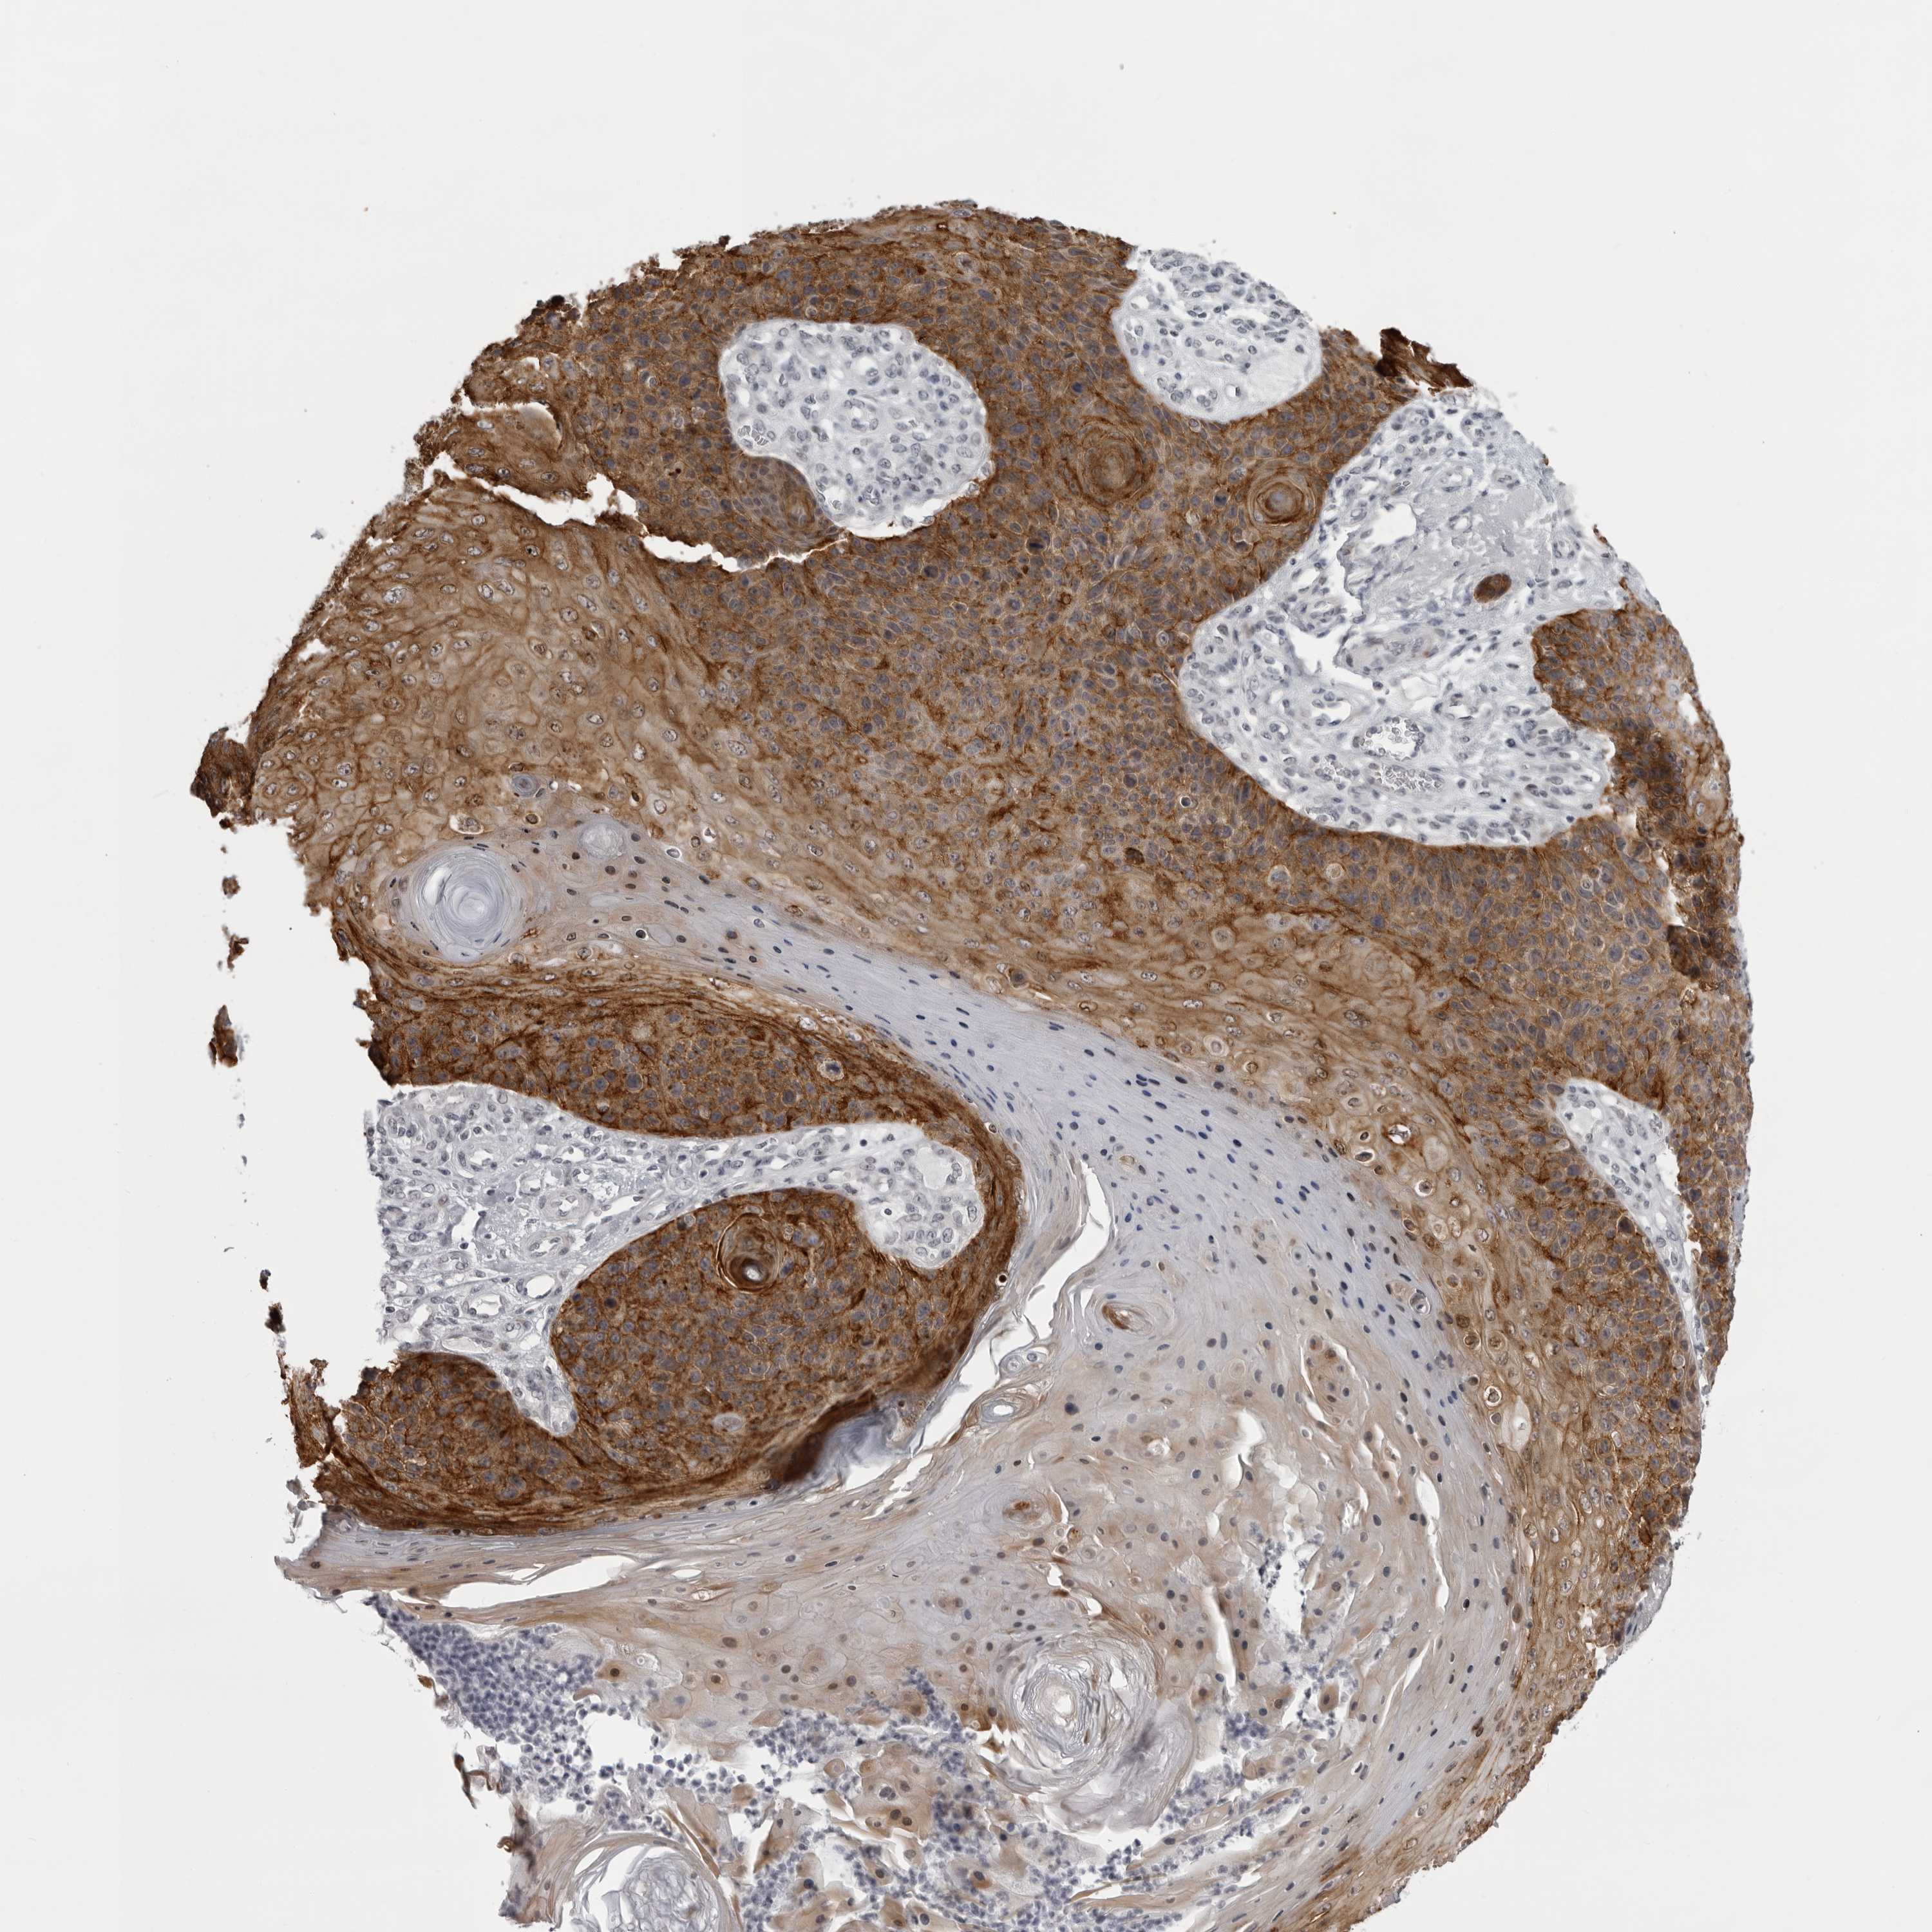

SKIN CANCER - Protein expressioni

A mouse-over function shows sample information and annotation data. Click on an image to view it in a full screen mode. Samples can be filtered based on level of antibody staining by selecting one or several of the following categories: high, medium, low and not detected. The assay and annotation is described here.

Each image is clickable and will lead to virtual microscopy that enables deeper exploration of all samples and also displays staining intensity scores, fraction scores and subcellular localization as well as patient and tissue information for each sample.

Antibody HPA028581

Staining

High

Intensity

Strong

Quantity

>75%

Location

Nuclear

Squamous cell carcinoma, NOS